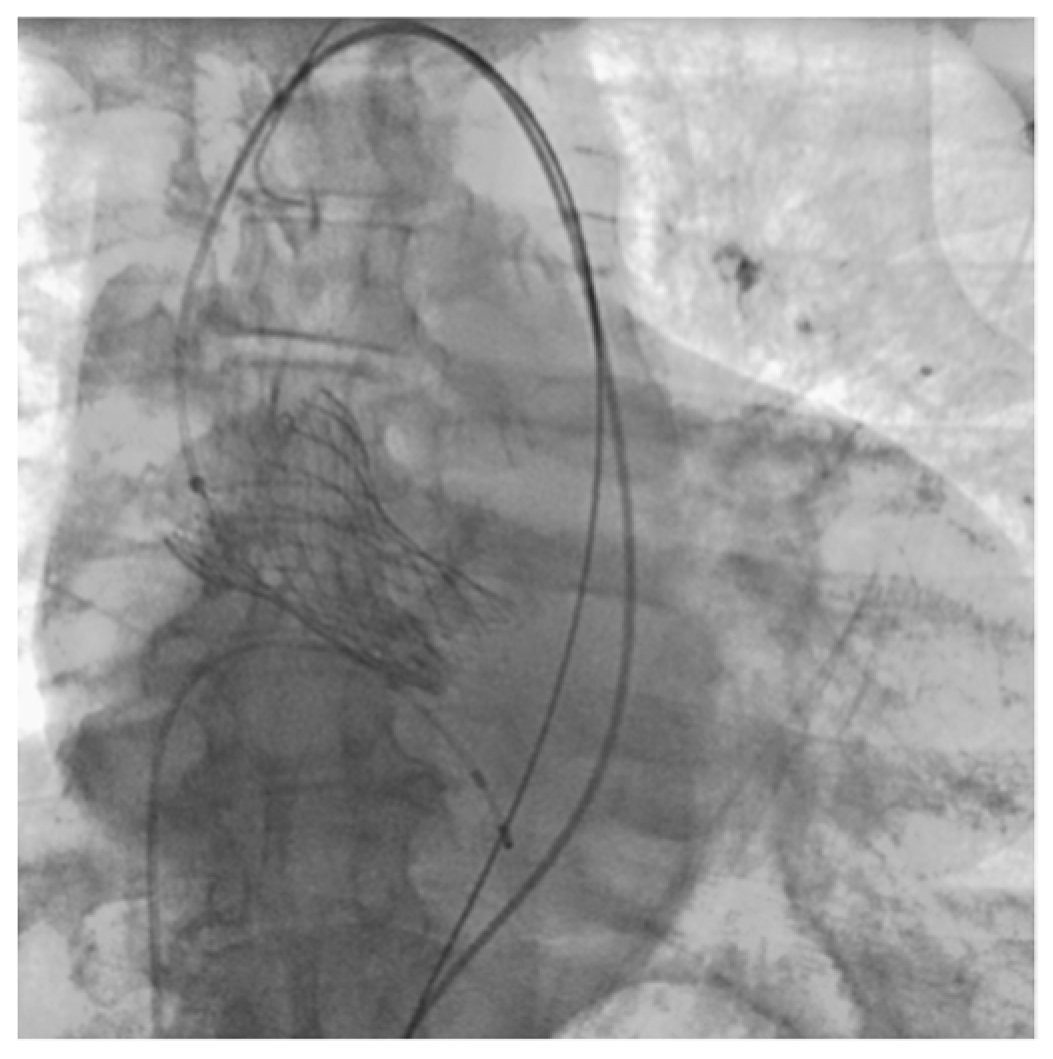

Patient M., a male, 73 years old, was admitted as planned to perform transcatheter aortic valve implantation (TAVI) for grade III aortic stenosis (mean gradient 41 mmHg, Aortic Valve Area index 0.44 cm2/m2). The patient has been suffering from 4th stage CKD for a long time, and the condition after surgical treatment and chemoradiotherapy for laryngeal cancer. The patient underwent the TAVI on the second day after hospitalization. The operation was performed under regional anesthesia and was performed normally (Figure 1).

Figure 1.

Final shooting after TAVI (Clinical Case 1, Patient M., 73 years old).